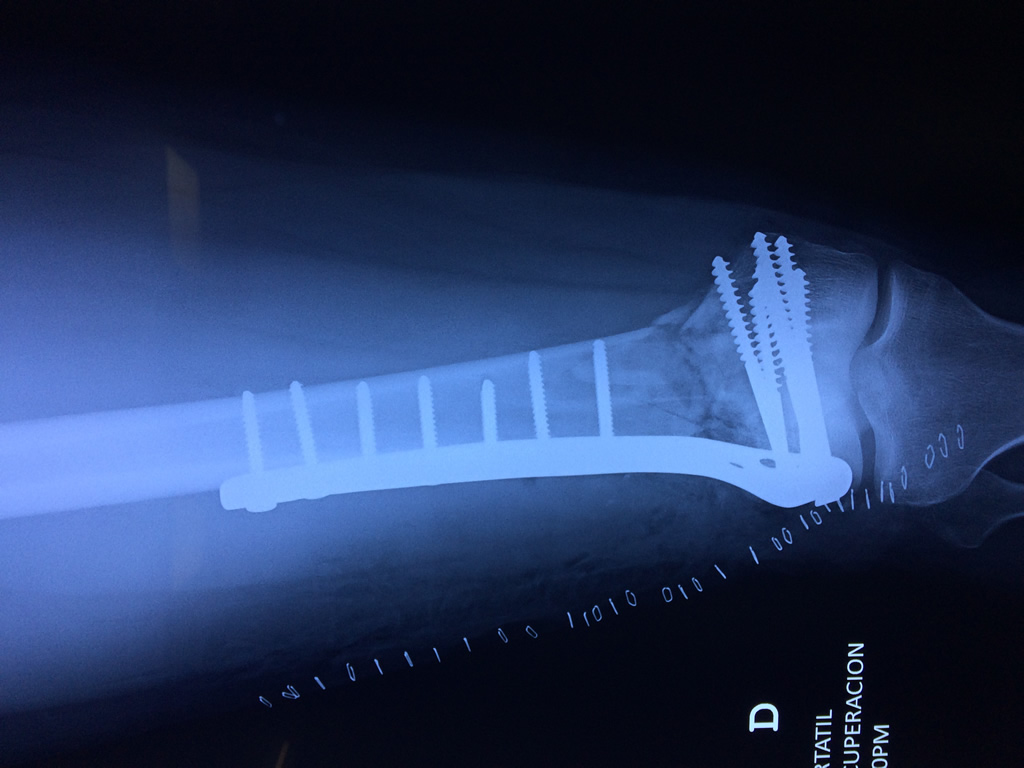

Cirugías de Peroné y Tibia